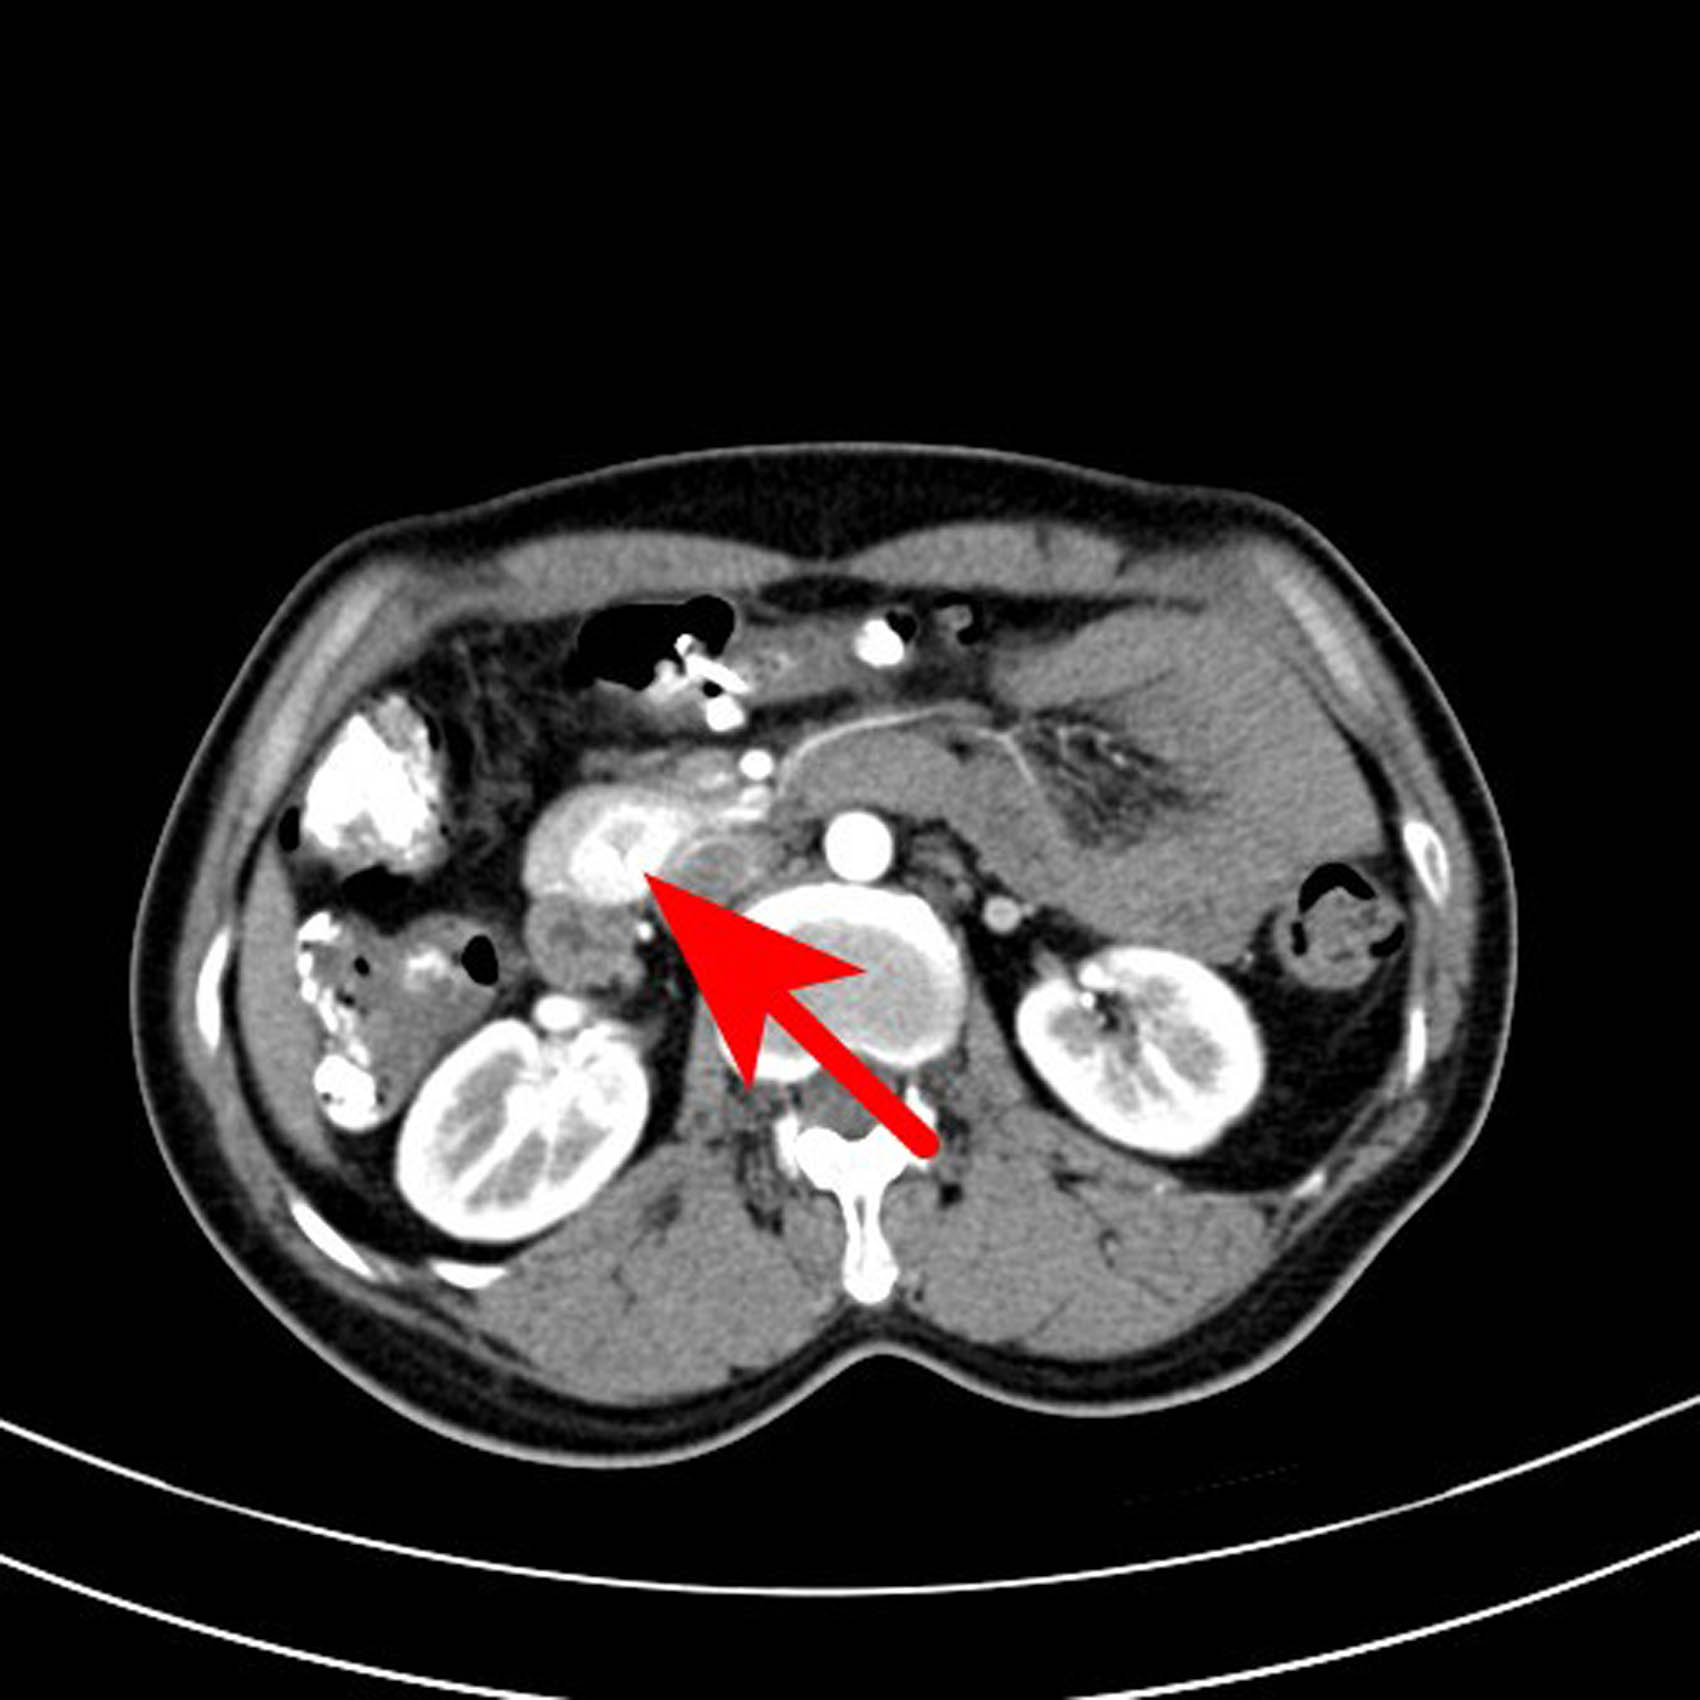

The following imaging tests were conducted. Specifically, the enhanced computed tomography (CT) of the entire abdomen revealed a slightly dense nodular shadow in the head of the pancreas with a maximum transverse diameter of approximately 19 mm, clear borders, and a small cystic hypodense shadow and punctate calcification shadow within, as well as an obviously unevenly enhanced lesion and no enhancement of the hypointense shadow. The CT value was approximately 58 HU on the conventional scan, 192 HU during the arterial phase, and 174 HU during the portal venous phase, and the hypodense shadow was not enhanced. A neuroendocrine tumor was considered (Figures 1–6).

Transverse axial scan of the arterial phase. The lesions showed uneven enhancement, the highest CT value reached 192 HU, and the low-density areas were not enhanced.